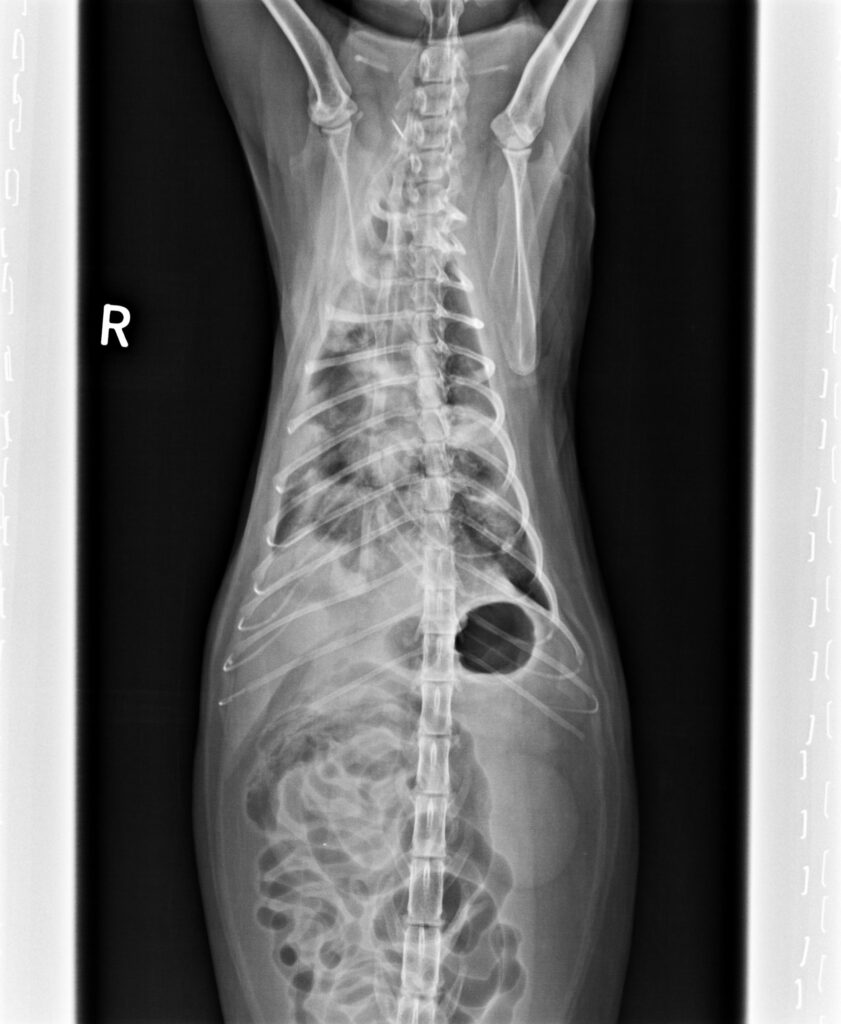

2023/5/11,一位街貓5.3公斤,3歲的橘貓因為很喘被附近的愛心人士帶來就診。愛心人士表示平時橘貓在他們家附近閒晃,他們就是定時餵食飼料,最近沒看到橘貓,再看到橘貓時就是一副很喘的樣子來找他們。愛心人士擔心之餘,經人介紹前來看診;在緊急為橘貓照完X光後,果然是罹患了肺炎。

胸腔X光1-3張見到瀰漫性結節團塊浸潤